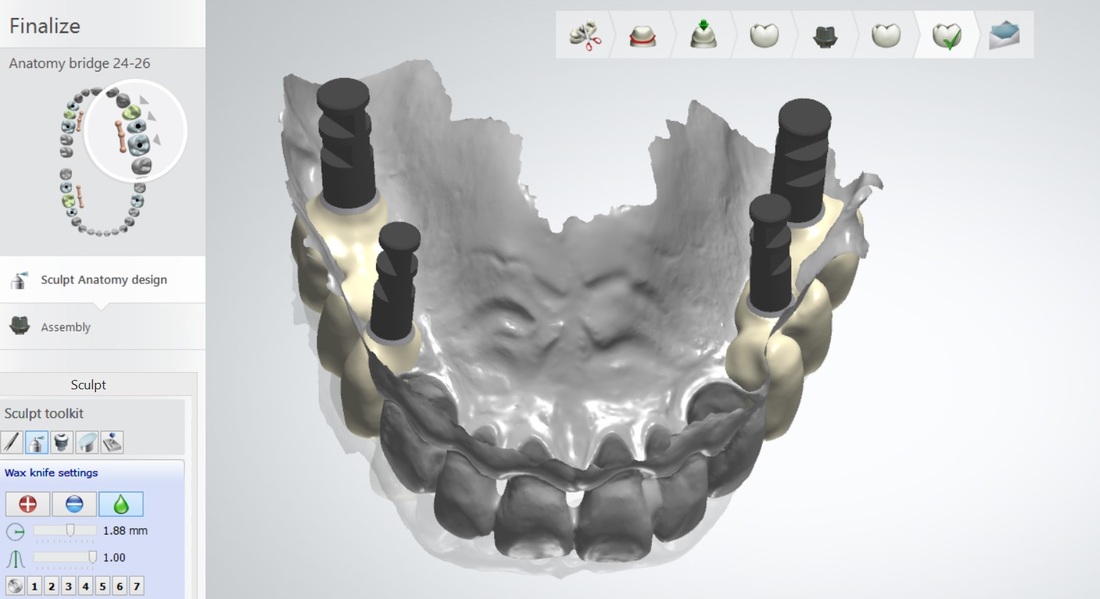

SIMULTANEOUS REHABILITATION OF ALL BACK TEETH

55 years old male had lost posterior teeth in all 4 quadrants, had collapsed bite with moderate TMJ arthrosis.

Dr. Andrews performed a SINGLE surgery – 7 implants placed along with few extractions and bi-lateral crestal sinus lifts.

Restored 100% digitally, utilizing CAD-CAM technologies, all screw-retained full contour zirconia implant crowns with life-time warranty for breaking/chipping.

Collapsed bite had been opened with Gneuromuscular technique. Occlusion was equilibrated 2 weeks after delivery with TENS. Cavities on front teeth were filled with tooth-colored composite fillings.